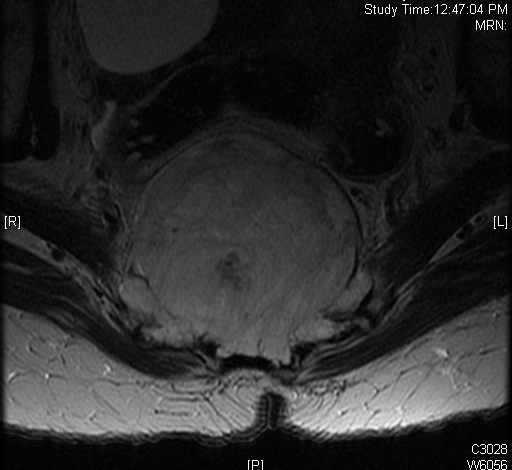

MRI (Fig. 4-10)

• Hyperintense on T2W (Fig. 8 & 9)

Fig. 4-10: MR image of a chordoma shows a destructive bone lesion in the sacrum that is hypointense on T1W images, hyperintense signal on T2W and enhancement of the lesion after gadolinium.